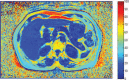

The aim of the study is to investigate if the fat content of the liver and pancreas may indicate impaired glucose tolerance (IGT) or type 2 diabetes mellitus (T2DM). A total of 83 subjects (34 men; aged 46.5 ± 13.5 years) were characterized as T2DM, IGT, or normal glucose tolerant (NGT). NGT individuals were stratified as <40 or ≥40 years. Standard laboratory tests were conducted for insulin resistance and β-cell dysfunction. The magnetic resonance imaging Dixon technique was used to determine fat distribution in the liver and pancreas. Correlations among liver and pancreatic fat volume fractions (LFVFs and PFVFs, respectively) and laboratory parameters were analyzed. Among the groups, fat distribution was consistent throughout sections of the liver and pancreas, and LFVFs closely correlated with PFVFs. LFVFs correlated more closely than PFVFs with insulin resistance and β-cell function. Both the LFVFs and PFVFs were the highest in the T2DM patients, less in the IGT, and least in the NGT; all differences were significant. The PFVFs of the NGT subjects ≥40 years were significantly higher than that of those <40 years. The fat content of the liver and pancreas, particularly the liver, may be a biomarker for IGT and T2DM.